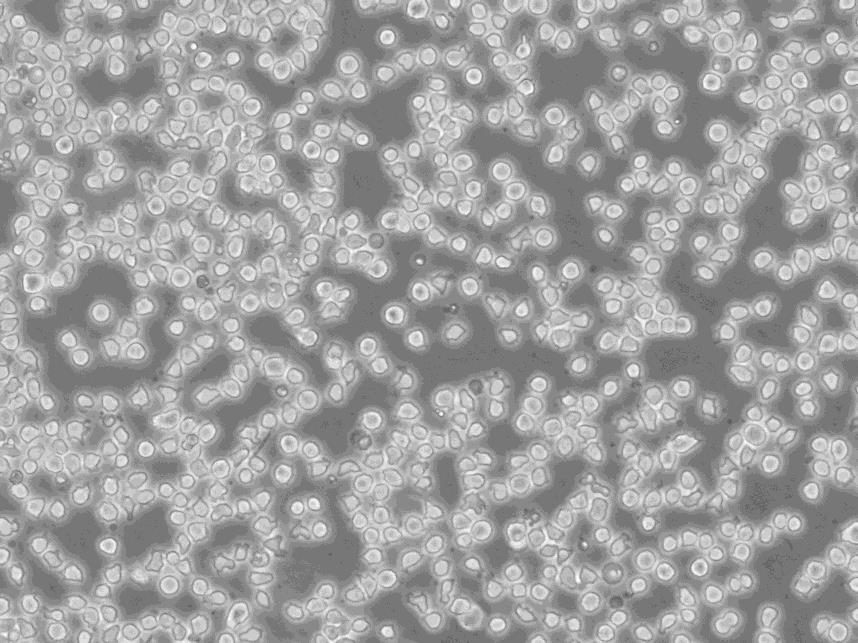

细胞形态:淋巴母细胞样

细胞生长:悬浮

细胞背景资料:间变性大细胞淋巴瘤;胸腔积液转移;男性

细胞生长特性:悬浮